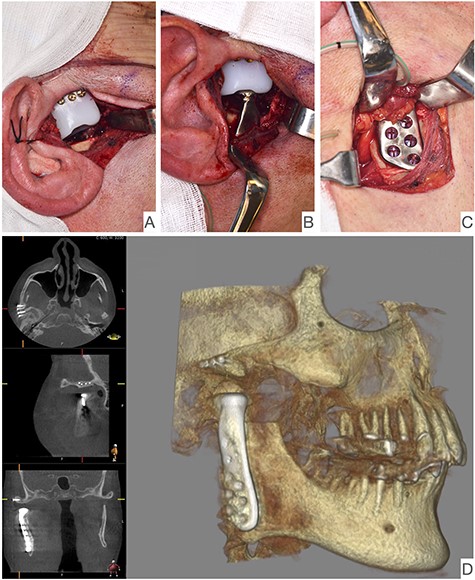

This report is about a 63-year-old patient suffering of bilateral deforming TMJ arthrosis (Wilkes-V) from a bilateral condylar fracture. In 2019 he presented himself to the Department of Oral and Maxillofacial Surgery, showing painful palpation above both TMJs and a severely decreased mouth opening (maximum interincisal distance of 1.5 cm). A computed tomography (CT) scan then revealed pathognomonic changes with flattening of the condyle and articular eminentia as well as partial ankylosis of the right TMJ (Fig. 1). Based on these findings, we decided for a bilateral TMJ-TJR. At this point, the patient only wanted one side replaced for the time being. After impressions were taken, plaster models were 3D-surface scanned and in combination with the CT dataset further processed by Zimmer-BiometTM (Warsaw, USA) for patient-specific TJR (PSI-TJR) fabrication. Another 3 months later, the TMJ-TJR of the right side could be carried out (Fig. 2). Postoperatively the patient received antibiotics for overall 7 days. Satisfied with the result, the patient requested reconstruction of the left TMJ 6 months later. With an improved mouth opening (2.8 cm), impressions were taken using an intraoral scanner. After PSI fabrication, the operation was carried out 9 months after (Fig. 3). Six weeks following surgery, the patient presented with a painful preauricular swelling on the left side, which was diagnosed as aseptic inflammation in the absence of erythema and pathologic joint puncture. Showing a periarticular edema, a broken screw and radial osteolysis around the drilling channels, a subsequent CT scan indicated the loosening of the ultra-high-molecular-weight-polyethylene (UHMWPE) fossa component (Fig. 4). In view of the long production time of new custom-made components and the damaged implant site, we decided to explant the fossa and to temporarily replace it with a non-fixed patient-specific spacer made of COPAL®-bone-cement (Fig. 5) (gentamicin and clindamycin additive) (Haereus; Hanau, Germany). The workflow included the surface scan of the original fossa-drilling template, the computer-aided design of a two-part press mould and the intraoperative fossa fabrication from COPAL®-bone-cement. With the use of a rubber elastic intermaxillary fixation, the vertical mandibular relation could be secured, painful movements and muscle shortening avoided and the risk of perioperative infection could be sufficiently minimized (Fig. 6). After 3 months without complications, the patient-specific COPAL® component could be removed and the new patient-specific UHMWPE fossa inserted within sufficiently regenerated bone (Fig. 7).

Intraoperative image showing the articular fossa (A) in combination with the articulating condylar component (B), the fixed ramus component (C) and the postoperative CBCT of the right side (D).

Shows postoperative CBCT after left TMJ replacement, 9 months after the right side.